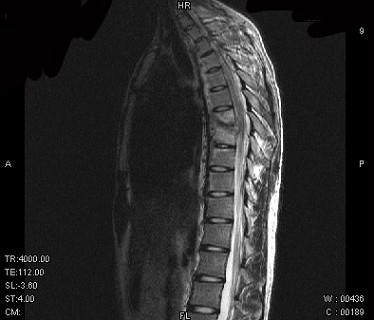

问题 男,21岁,有午后发热,夜间盗汗等,胸部疼痛,活动时加重,休息后减轻,请结合所提供图像,选择最佳答案 ( )

选项 A、骨巨细胞瘤 B、胸椎结核 C、胸椎骨转移 D、胸椎退行性变 E、骨髓瘤

答案 B